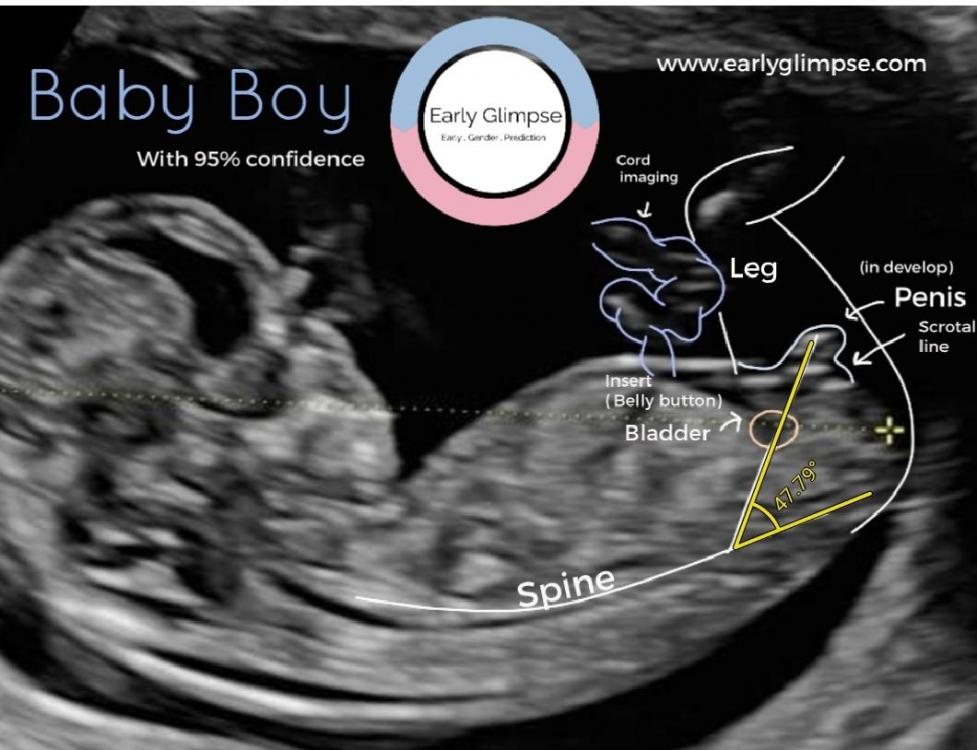

Strikkesokken Skrevet 24. juni 2020 Forfatter #999 Skrevet 24. juni 2020 15 timer siden, Mumsy skrev: Gratulerer med ny bil! Så spennende med OUL 😁 Jeg skal forøvrig på privat UL i morgen og er også 100% sikker på at jeg har en gutt i magen. Og ikke nok med det, jeg jakter også på gamle guttenavn, slik at han kan matche storebror på et vis 😋 Liker også Albert 😊 Ellers har jeg Gustav, Nore, Sigve, Emrik og Olai på lista. For min del holder jeg en knapp på Nore, syns det var så kult fra første gang jeg fant det! Men mannen syns det lignet litt mye på Nora, eller Nure, jeg tenker at det ikke ligner litt en gang 😂 Takk!! Såå spennende med OUL! Du må oppdatere på hvordan det går. Har du dagbok her inne? Nore var kult! Det har jeg ikke hørt før. Men det kommer jeg heller aldri til å få mannen med på😅 han hadde nok også sagt "Nora?!". O sitt navn blir litt for likt Olai, men det er også veldig fint! Syns Olav er fint og, men mannen har en kompis som heter det så det går ikke. Jørgen liker jeg og, men han har kompis som heter det og, selvfølgelig 🙄 Navn er så vanskelig!! ----- T-24 timer til OUL! Gleder meg 😁 igår klarte jeg ikke å dy meg, og sendte inn bilder fra TUL til to ulike sider som driver med Nub Theory. Det er en teori som går ut på at nuben (tissen) til gutter og jenter vinkler ulikt mellom uke 12-14. Jeg har hele tiden trodd det er tissen jeg ser på TUL bildet, og ville ha det bekreftet. Isåfall er det ihvertfall ingen tvil om at det er en guttebass på vei! Resultatet: 95% og 98% sikkerhet, de kan ikke ta feil da. Like før jeg bestilte gutteklær på nett igår kveld 😅